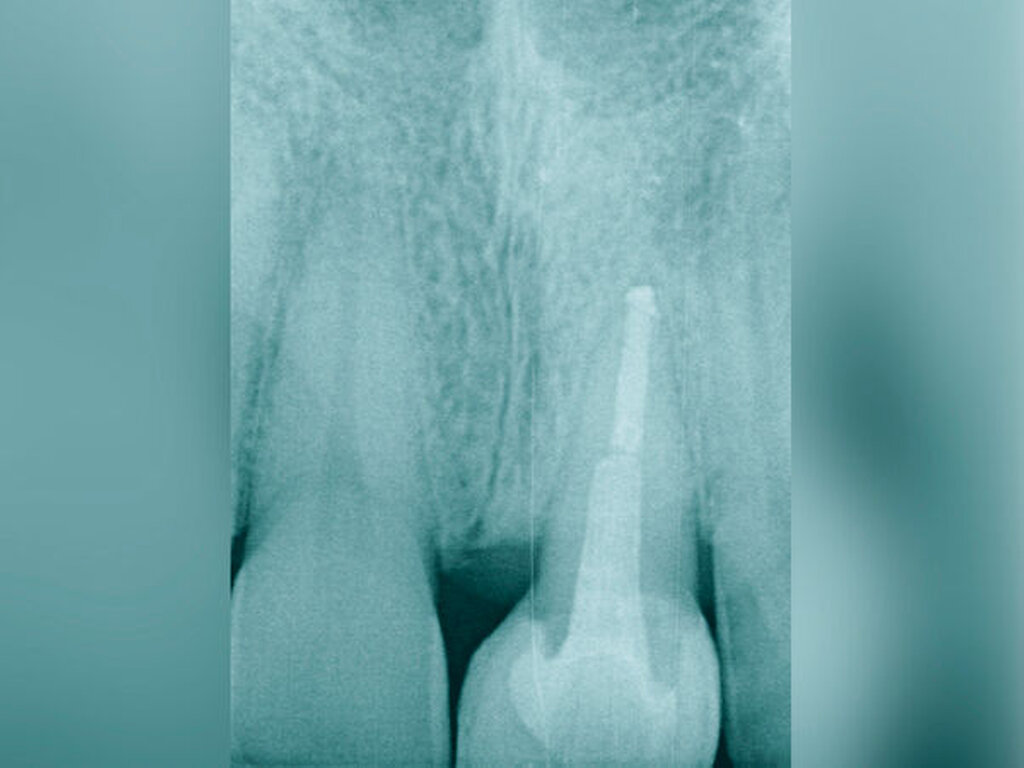

Bei der chirurgischen Extrusion (Synonym: intra-alveoläre Transplantation) wird der betroffene Zahn oder die betroffene Wurzel chirurgisch weiter koronal positioniert, um die Anfertigung einer adäquaten Restauration zu ermöglichen. Ihr biologisches Prinzip ist eingehend beschrieben worden mit guten Erfolgen im Tiermodell [Oikarinen et al., 1996] und in der klinischen Anwendung [Caliskan et al., 1999; Das und Muthu, 1999; Krug et al., 2018]. Die Technik wird bisher kaum in der zahnärztlichen Praxis angewendet, vermutlich aufgrund der begrenzten Vorhersagbarkeit, einen schwer kompromittierten Zahn oder eine Zahnwurzel erhalten zu können, wenn auf konventionelle Art und Weise extrahiert wird. Zum einen besteht das Risiko, durch die Extraktion eine Zahnfraktur zu verursachen, die den Zahnverlust zur Folge hat. Zum anderen führt die Anwendung von Luxatoren, Elevatoren oder Periotomen zu einer Aufdehnung der Alveole sowie zu Schäden am parodontalen Gewebe und gegebenenfalls an der Zahnwurzel selbst. Die Herausforderungen bei einer Zahnmobilisation für eine chirurgische Extrusion bestehen darin, weiteren Schaden an den Strukturen von Zahnhartsubstanz, Knochen und parodontalem Ligament zu vermeiden. Gelingt dies, können deren Hauptrisiken wie Zahnfraktur und progressive Wurzelresorption minimiert werden [Elkhadem et al., 2014].

Zur chirurgischen Extrusion werden meist Extraktionszangen verwendet. Die Zahnwurzel wird dabei idealerweise mit einer diamantierten Zange gefasst und durch Rotation vorsichtig entfernt. Insbesondere bei Zähnen mit runden Wurzeln ist diese Technik auch weitgehend schonend für das parodontale Ligament. Der forcierte Einsatz von Hebeln oder Luxationsbewegungen ist zu vermeiden, da diese zu parodontalen Schäden auf der Wurzeloberfläche führen können und somit die parodontale Heilung nach Replantation gefährden.

Eine weitere Möglichkeit, tief zerstörte Zähne möglichst schonend chirurgisch zu extrudieren, basiert auf axialen Zugsystemen (Abbildungen 2 bis 4). Diese erscheinen vorteilhaft bei sehr schwierigen Fällen, zum Beispiel bei Zähnen mit fehlendem Ansatzpunkt für die Zange sowie bei langen oder sehr ovalen Wurzeln. Axiale Zugsysteme ermöglichen die Übertragung von Zugkräften auf die Zahnwurzel, ohne die Alveole unnötig zu dehnen. Dazu wird eine spezielle Schraube in den Wurzelkanal eingebracht und das Gewinde der Schraube für eine ausreichende Friktion fingerfest eingedreht. An diese Schraube wird ein gerätespezifisches Zugsystem angelegt. Durch rein axial wirkende Zugkräfte werden traumatische Effekte auf Knochen und Wurzeloberfläche während der Zahnmobilisation minimiert. Gegebenenfalls können feine Luxatoren vorsichtig unterstützend eingesetzt werden. Im Tiermodell wurde an extrahierten und wieder replantierten Zähnen mit ovalem Querschnitt gezeigt, dass der Verlust von Zementoblasten auf der Wurzeloberfläche geringer ist, wenn ein axiales Zugsystem anstatt einer Extraktionszange verwendet wird.

Die wesentliche technische Komplikation stellt das unverhältnismäßige Erweitern des Wurzelkanals für die Retention des Zughilfsmittels – zum Beispiel der Benex-Schraube – dar. Der Behandler sollte hier unter besonderer Vorsicht den bereits instrumentierten und präparierten (vorgegebenen) Wurzelkanal als Bohr- und Zugpfad für die Extrusion nutzen. Auf die Schonung der gesunden Zahnhartsubstanz muss geachtet werden. Die Bohrachse für die Ausrichtung der Zugschraube muss mit dem koronal gelegenen Hauptpfad des Wurzelkanals übereinstimmen. Zudem ist für das Erzielen einer ausreichenden Retention der Schraube ein gewisses Maß an Feingefühl und Taktilität vom Behandler erforderlich. Eine neue Schraube erfüllt die Vorbedingung eines schneidfreudigen Gewindes und damit eines guten Halts im Zahn am besten.